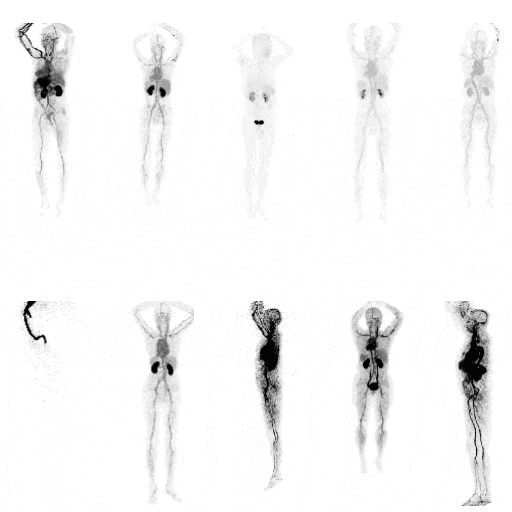

The PET imaging of a novel tracer.

Parametric imaging of a patient.